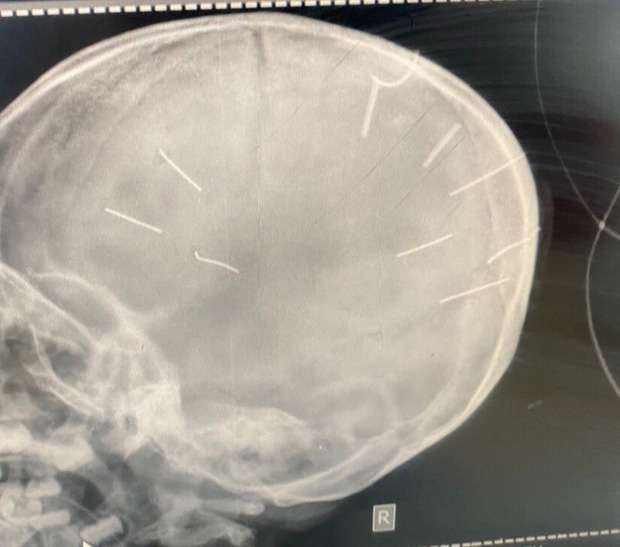

Hình ảnh chụp X-Quang hộp sọ bệnh nhân với 9 hình thể nghi là đinh (Ảnh: Bệnh viện Đa khoa huyện Thạch Thất cung cấp)

Tối 19/1, Công an huyện Thạch Thất, Hà Nội, cho biết đơn vị đã bàn giao người tình của mẹ bé Đ.N.A. cho Phòng Cảnh sát hình sự, Công an TP. Hà Nội để điều tra liên quan vụ bé gái 3 tuổi nghi bị bạo hành, có 9 vật thể nghi là đinh trong sọ não. H. được xác định là nghi phạm chính trong việc bé A. nghi bị đinh bắn vào đầu.